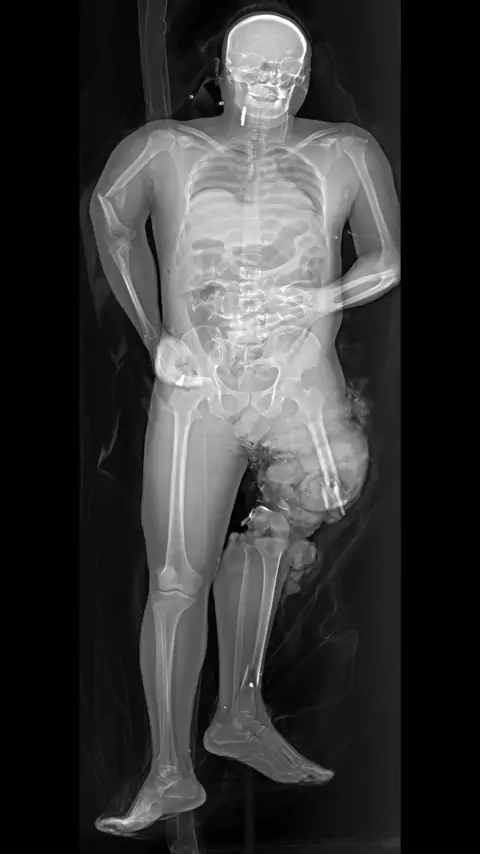

The effectiveness and high speed of Lodox imaging dramatically reduce the resuscitation time of patients with major injury, and allow imaging of a large number of patients in a very short time. The full-body image can show injuries throughout the body, providing a complete picture of a patient’s medical state that will guide diagnosis, while providing space for resuscitation at all times and providing immediate insight into what further imaging, and treatment, may be necessary. Sc: lodox - crit...